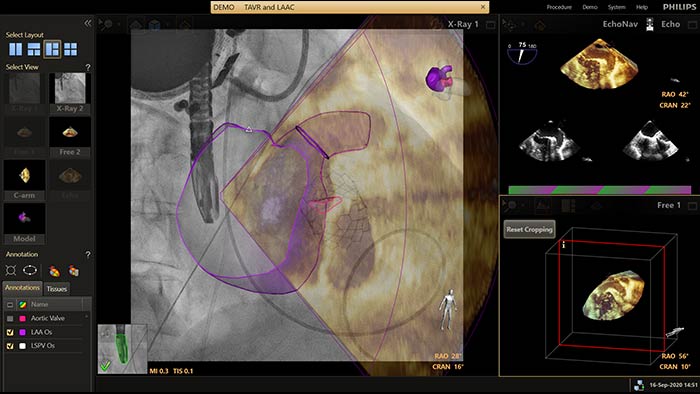

EchoNavigator riorienta e combina le informazioni ecografiche e radiografiche in un'unica visualizzazione aumentata, per la guida e la valutazione della relazione dispositivo-tessuto. Nei casi di occlusione dell'auricola sinistra, EchoNavigator garantisce livelli elevati di affidabilità ed efficienza per le seguenti operazioni:

Soluzioni per le procedure TAVR e TAVI offerte dalla terapia guidata da immagini di Philips.